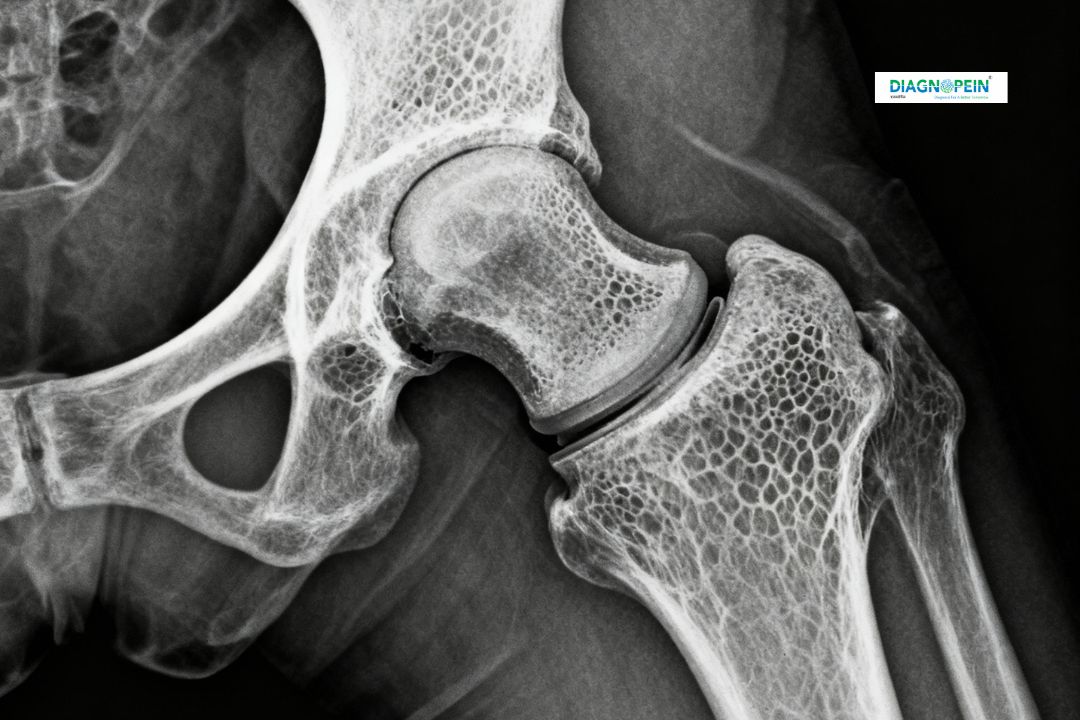

An X-Ray Hip Joint One View is a quick and non-invasive imaging test used to examine the bones and structure of the hip region. It helps doctors assess conditions like fractures, bone deformities, arthritis, and joint alignment issues. At Diagnopein in Karad, our advanced digital X-ray facilities ensure high-quality images with minimal radiation exposure and fast reporting.

This X-ray provides a direct single-view image of the hip joint, allowing precise evaluation of the bones and surrounding joint space. The procedure is simple, safe, and often the first imaging choice for patients with hip pain or injury.

The X-Ray Hip Joint One View captures key anatomical structures including:

1. Femoral head and neck alignment

2. Acetabulum (hip socket) clarity

3. Joint space width and symmetry

4. Detection of fractures, calcification, or soft tissue swelling

5. Bone density and surface irregularities

These parameters help doctors evaluate bone health and detect any degenerative or traumatic changes effectively.